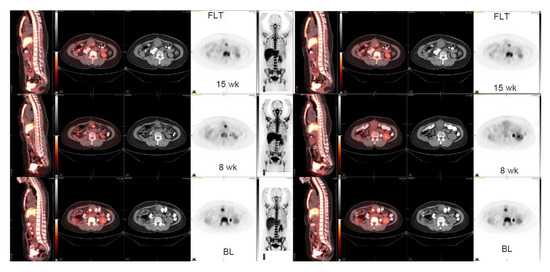

| 48/F | Malignant fibrous histiocytoma (MFH), RLL mass | 4.1 3.2 × 2.5 | 3.0 3.5 × 2.8 2 weeks | 7.6 5.0 × 3.9 8 weeks | +85% | |

| 49/F | Uterine leiomyosarcoma, RLL mass | 8.8 4.9 × 3.7 | 10.7 4.9 × 3.8 2 weeks | 11.2 5.2 × 4.2 8 weeks | +27% | |

| 49/F | Uterine leiomyosarcoma, LLL mass | 8.0 4.2 × 3.6 | 7.8 4.2 × 3.5 2 weeks | 7.6 4.6 × 3.7 8 weeks | −5% |